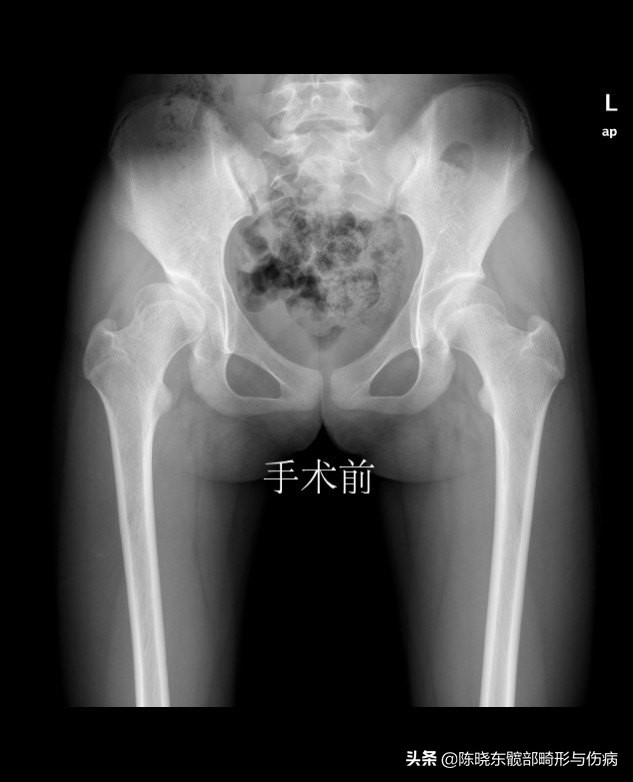

上图为23 岁青年女性,右侧腹股沟疼痛半年,曾经当作滑膜炎治疗三个月无效。来我院行髋臼周围截骨术,术后看见髋臼对股骨头的覆盖包容明显改善,疼痛消失,恢复正常的生活/学习/娱乐。